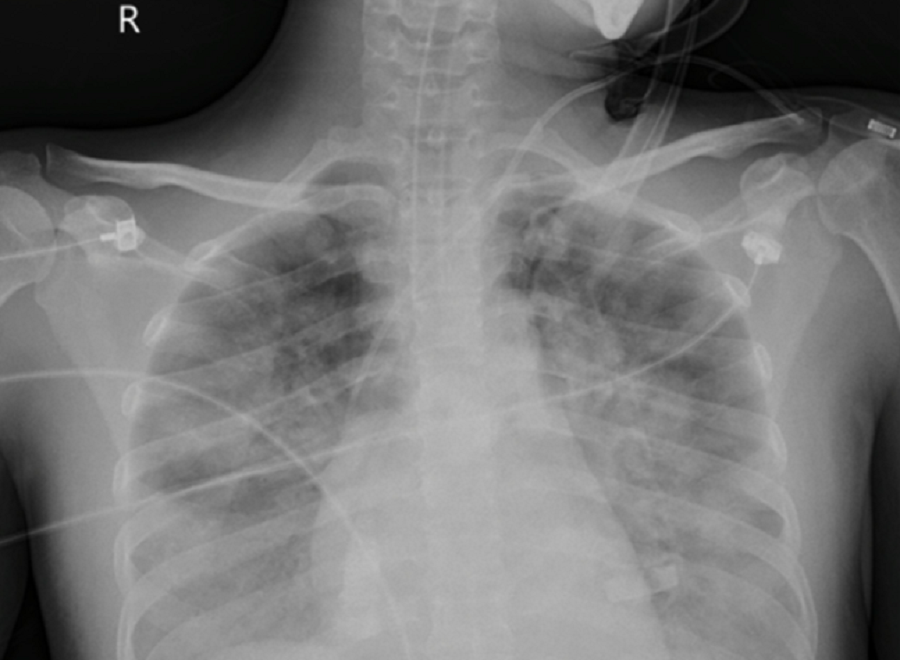

| Phổi của nữ bệnh nhân bị tổn thương rất nặng cả hai bên phổi do nhiễm 'vi khuẩn ăn thịt người' |

Tại đây, bệnh nhân được hồi sức chuyên sâu. Qua thăm khám, chẩn đoán hình ảnh, các bác sĩ phát hiện người bệnh bị tổn thương phổi lan tỏa hai bên chiếm gần 70% thể tích cả hai phổi. Người bệnh đã được đặt hệ thống oxy hóa qua màng ngoài cơ thể (VV-ECMO).